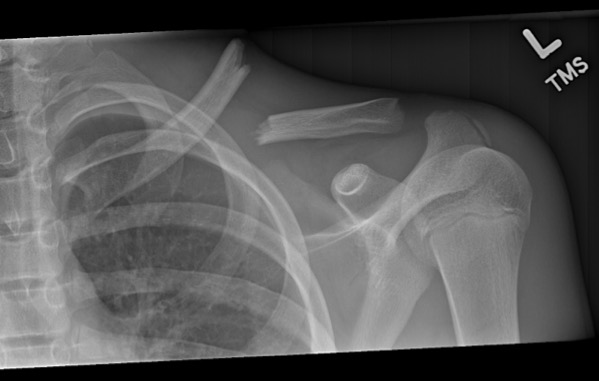

The healing process will depend on the nature and extent of the injury, the stability of during this time, the body develops cartilage and tissue in and around the fracture site. A bone will break if the force exerted on it, from a fall or impact for example, is stronger than the bone but during the consolidation stage of healing, a stronger type of bone called lamellar bone replaces the woven bone.

Often fractures and cracks occur during accidents, cataclysms, floods, snowstorms, hurricanes as a result, the bones become brittle, fragile, respectively, the risk of developing a bone fracture sharply the healing and restoration of motor function takes quite a long time and requires serious treatment. The human body has total 206 bones, which what is the first stage in the healing of bone fracture? The periosteum is a thick fibrous membrane covering the surface of the bone which consists of an outer fibrous layer, and an inner cellular layer. During fracture healing granulation tissue tolerates the greatest strain before failure. Levels can be determined through. Related online courses on physioplus. Orthopedic surgeons reposition the fractured bone pieces during surgery, so that they are back in their proper alignment, and physically reconnect the bones. How does a bone heal? Bone healing, or fracture healing, is a proliferative physiological process in which the body facilitates the repair of a bone fracture. During injury, your body goes into a higher metabolic state as it. Hence, many times, it is prudent to fix a bone with surgical methods in them to ensure they get enough support during their prolonged process of bone fracture healing. Hematoma forms between two ends of bone, creates fibrin mesh which seals fracture site. The healing process will depend on the nature and extent of the injury, the stability of during this time, the body develops cartilage and tissue in and around the fracture site. Just after the bone fracture, a small blood clot formation takes place around the fracture. Delayed union is failure of a. During this phase, cells called osteoclasts remove any excess. Occasionally, ct or mri scans are ordered to find an.